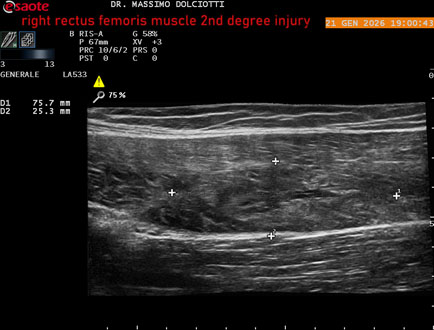

Data inserimento: 23/01/2026

Ecografia del: 21/01/2025

Strumento: Esaote MyLab Eight

Sonda: Lineare Multifrequenza 3-13 MHz

Età Paziente: M 23 anni

Motivazione dell'esame: dolore al terzo prossimale della coscia destra da tre giornii.

Commento all'esame: le immagini ed il video documentano, al terzo prossimale del muscolo retto femorale destro, area disomogenea, ipoecogena, delle dimensioni di 35 mm per uno spessore di 18 mm, misura ottenuta per asse corto o trasversale, e di 71 mm x 20 mm, misura ottenuta per asse lungo o longitudinale, da ricondurre a lesione muscolare di 2° grado con modica raccolta sieroematica intramuscolare.

Conclusioni: lesione di 2° grado del muscolo retto femorale destro (2nd degree injury of the right rectus femoris muscle).